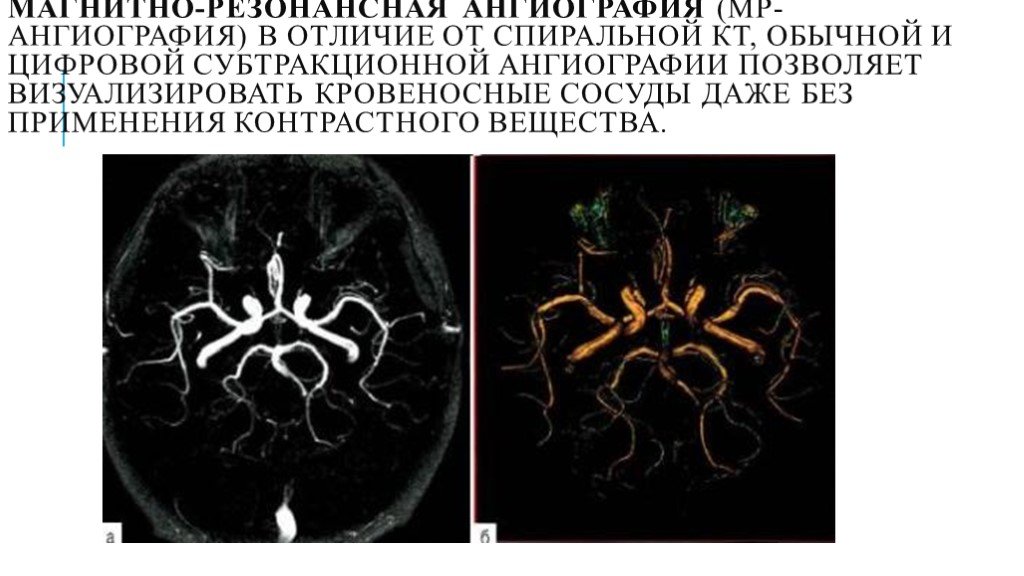

Компьютерная томография в неврологии презентация - 86 фото